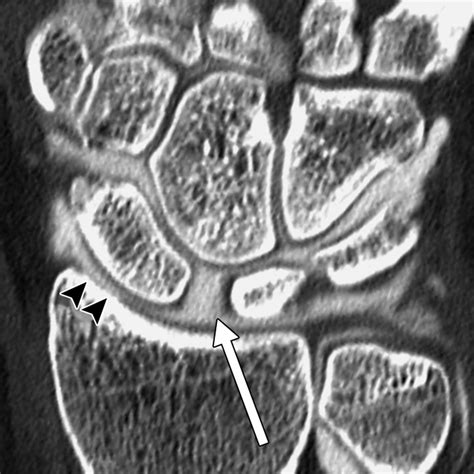

Diagnosing this condition requires a comprehensive physical examination combined with advanced imaging. Physicians typically rely on standard X-rays, which often reveal the characteristic gap in the scaphoid and the narrowing of the joint space. In more complex cases, a CT scan or MRI may be ordered to assess the exact degree of cartilage degradation and to plan potential surgical interventions.

• scaphoid nonunion advanced collapse radiology